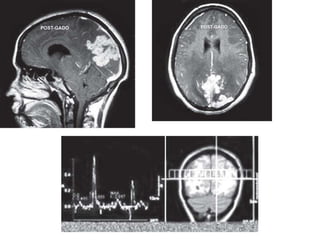

T1W sagittal (A) and T2W axial (B) MR images showing

multiple lesions having a hypointense center on T1 and hyperintense

center on T2W images with perilesional edema. The collagenous capsule

of the lesions is iso to slightly hyperintense on T1 and hypointense on

T2W images. Mass effect on the ipsilateral ventricular system with

dilatation of the contralateral temporal horn is seen — multiple brain

abscesses

Proton MR spectroscopy and diffusion

weighted imaging

• In vivo proton MR spectroscopy has been found

to be useful in the differentiation of brain abscess

from other cystic mass lesions

• In an untreated abscess, the usual metabolites

observed are succinate (2.4 ppm), acetate (1.92

ppm), lactate/lipids (1.3 ppm),

leucine/isoleucine/valine (0.85 ppm), glycine (3.5

ppm), alanine (1.5 ppm) and other amino acids

• Demonstration of these metabolites is considered

specific of an abscess and has not been observed

in a cystic neoplasm.